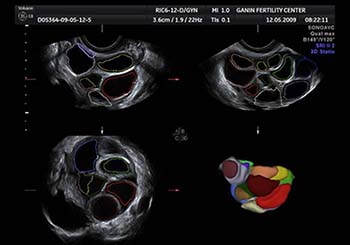

* لأن إمكانيات الجهاز الخاص بالسونار الثلاثي الأبعاد له القدرة في دراسة الأوعية الدموية الدقيقة الموجودة بالرحم، وهو ما لا يتوافر للأجهزة العادية. بل أن الجيل الأخير من الأجهزة الحديثة المتطورة لأجهزة السونار ثلاثي الأبعاد (والتي تم إدخالها في مركز جنين حديثا) أضافة إمكانية التقييم الكمي والنوعي للأوعية الدموية التي تغذي الرحم والمبيضين وهو ما لا يتوافر حتي في الأجهزة العادية ثنائية الأبعاد التي يمكنها دراسة الأوعية الدموية. متابعة التبويض بإستخدام برنامج خاص يتم من خلاله التحديد التلقائي لحجم والأبعاد الخاصة بالحويصلات التي تنمو داخلها البويضات، وهو ما يعني سرعة في الأداء وأيضا دقة في التقييم والذي يعكس بالتالي على جودة البويضات والتحديد الأفضل لتوقيت نضوجها.